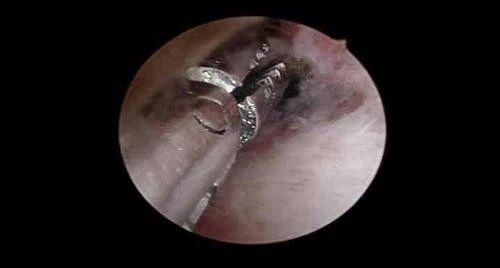

宫腔镜手术中

宫腔镜手术是指用宫腔镜进行的微创手术,通过阴道、宫颈口用纤维光源进入宫腔,镜子基本是直的,有的带有角度,但不粗,大约像一次性笔粗细,有放大功能,可以清晰观察子宫腔形态,宫腔内有无息肉、黏膜下肌瘤、有无纵隔或剖腹产切口憩室等,利用微创手术器械进行恢复子宫腔形态或切除息肉等手术。